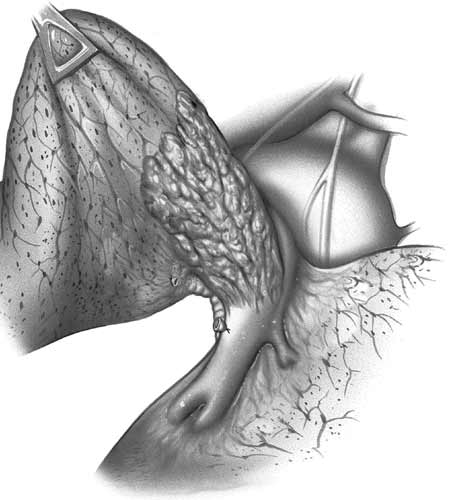

| Figure 9: Line drawing (left) and intraoperative image (right) showing the usual pattern of infiltration of the interlobar portion of the pulmonary artery posterior to the left upper lobe bronchus.* | |

During resection control of the main pulmonary artery and the inferior pulmonary vein is obtained. The superior pulmonary vein is divided in a standard fashion. Pulmonary arterial tissue is resected en bloc with the specimen. After the resection, an oval defect oriented along the PA axis remains, even if the resected portion was circular in shape (Figure 10). This is due to the tension applied on the vessel by the lower lobe. The patch should be tailored according to the size and shape of the resected portion rather than according to the PA defect (Figure 11). After the patch is secured to the artery by 5/0 or 6/0 monofilament running suture, the PA is declamped (Figure 12). The suture line must be checked carefully for oozing, which might not be evident due to the low PA pressure. Also it is important to check the position of the artery after reexpansion of the lower lobe, for kinking might occur.

Infiltration of the PA on the right side requiring arterial reconstruction is less frequent. Partial resection of the PA often is performed in conjunction with right upper lobe sleeve resection (Figure 13). After right upper sleeve lobectomy en bloc with partial resection of the PA, the stump of the main bronchus and the PA defect are left open in the field (Figure 14). Harvesting of the pericardium is performed as above, based on the size of the portion of the resected pulmonary artery. Patch reconstruction of the PA is completed as above before reimplantation of the bronchus to reduce the arterial clamping time (Figure 15).